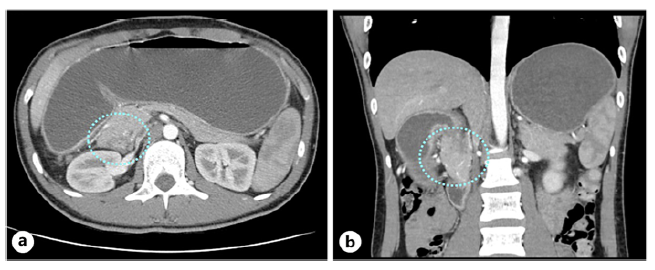

A previously healthy 22-year-old male presented to our hospital with a 2-month history of heartburn, postprandial vomiting, and significant weight loss. Physical examination revealed a soft, non-tender abdomen. Laboratory tests showed microcytic anemia (Hb 11.3 g/dL, MCV 66 fL) and thrombocytosis (544 × 109/L), with normal amylase and lipase levels. Upper endoscopy identified antral ulcerations and a severely stenotic pylorus (Fig. 1), preventing further scope advancement. A subsequent abdominal computed tomography scan revealed marked gastric distension, a significant reduction in the caliber of the second portion of the duodenum, and abnormal projections of the pancreatic head wrapping the descending part of the duodenum (Fig. 2).

Fig. 2 CT scan - axial (a) and coronal (b) planes - showing gastric distension and stenosis of the second portion of the duodenum with abnormal pancreatic head tissue wrapping the descending part of the duodenum (dotted blue circle). CT, computed tomography.